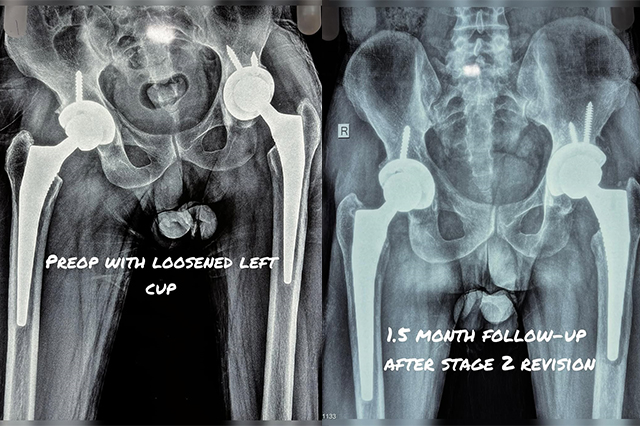

Hip-Knee-Replacement